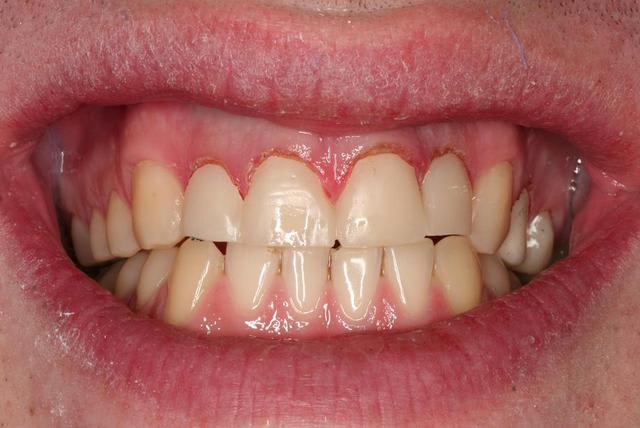

5 cicatrisation à 3 jours (pas mal, non?)